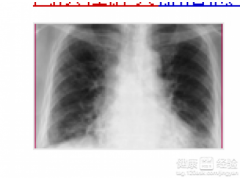

华中呼吸病诊疗中心提供的肺间质性肺炎治疗主要是针对患肺间质性肺炎的人群的,治疗周期大概为1-30天。我机构始终秉持着中医治疗,打通经络,清肺排有害,化痰定喘,肺腑穴位贴药,配合煎药泡脚的特色服务,所提供的肺间质性肺炎治疗在西安市拥有很高的认知度。